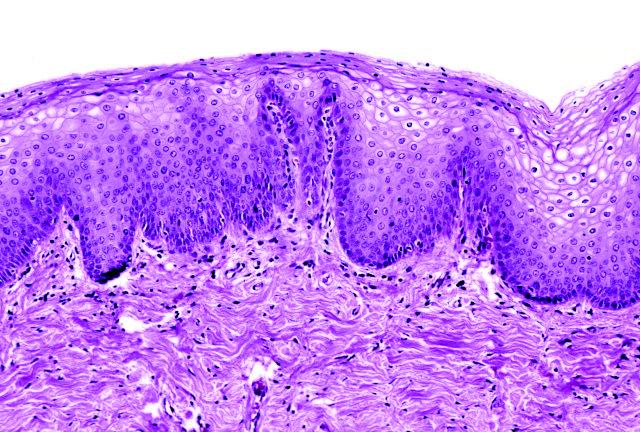

Základem je zdravá sliznice

Poševní sliznice je tvořena několika vrstvami, které tvoří tzv. dlaždicový epitel o tloušťce 3 až 4 mm. Její povrch je osídlen celou řadou bakterií, a to jak těmi prospěšnými, tak nepřátelskými tzv. patogenními, které mohou vyvolat infekci. Ty jsou samozřejmě v menšině, nebo se vyskytují ojediněle. Obě skupiny bakterií žijí v rovnováze a když je vše v pořádku, patogenní bakterie nemají prostor a podmínky na to, aby se dostatečně pomnožily a vyvolaly onemocnění. Jako „potrava“ pro zdraví prospěšné bakterie (laktobacily) slouží živočišný škrob – glykogen uložený v buňkách dlaždicového epitelu. Při jeho štěpení vzniká kyselina mléčná zajišťující kyselé prostředí, které prospívá koloniím laktobacilů a naopak škodí patogenním bakteriím. Pokud sliznice nemá zajištěnou správnou výživu, tloušťku a dostatečné množství glykogenu dochází k narušení vaginální mikroflóry.